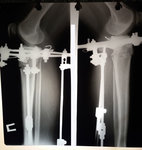

Рентген в 20 дней.

Вложения

20170906_111206.jpg

20170906_111223.jpg